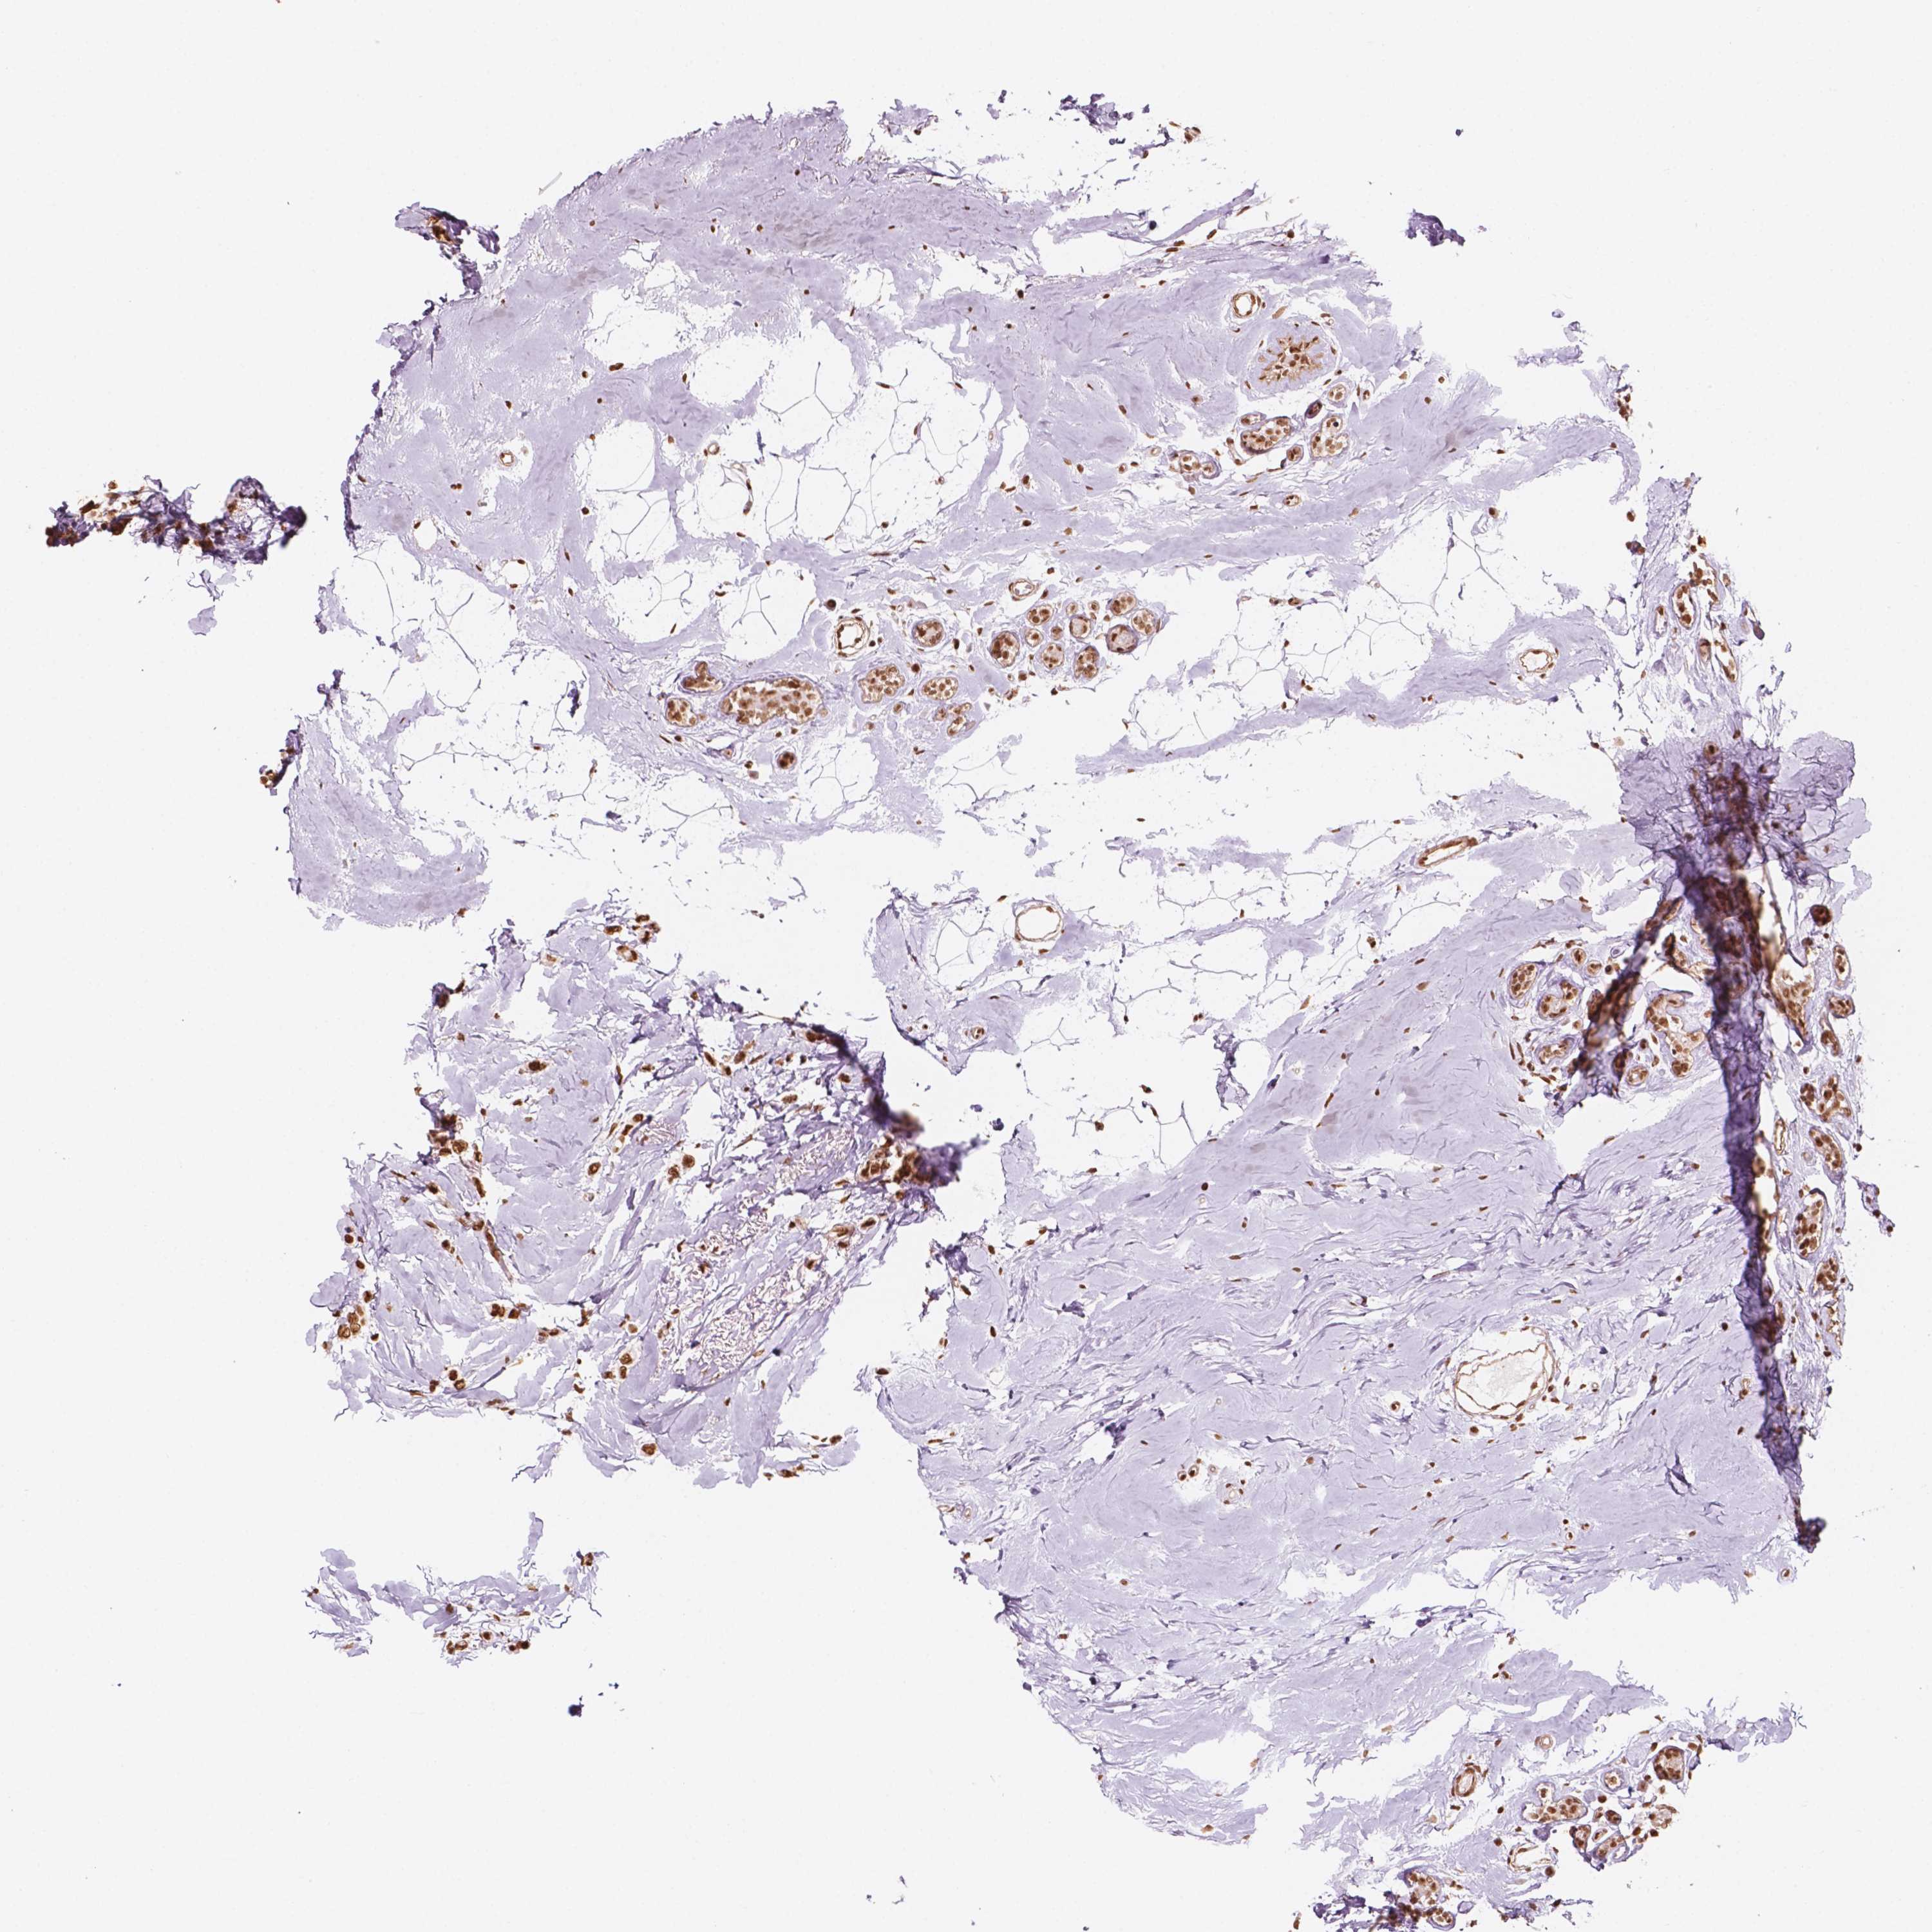

CANCER BREAST CANCER Show tissue menu

BRCA TCGA BRCA VALIDATION PROTEIN EXPRESSION